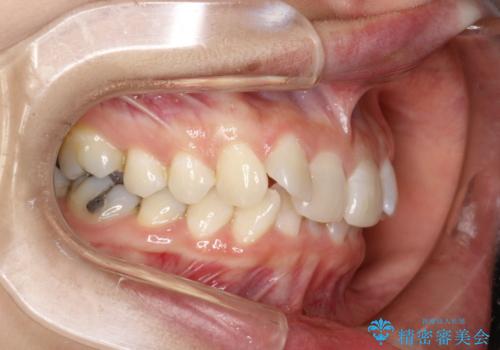

前歯のガタガタをインビザラインで矯正

- 前歯のがたつきを気にされて来院されました。

右上の前から2番目の歯が前方に大きく傾いており、下の前歯もガタガタしていました。

インビザラインにて、歯と歯のあいだをわずかに削り並べる計画としました。

しっかりとマウスピースを使用していただけたので、順調に治療を終えることができました